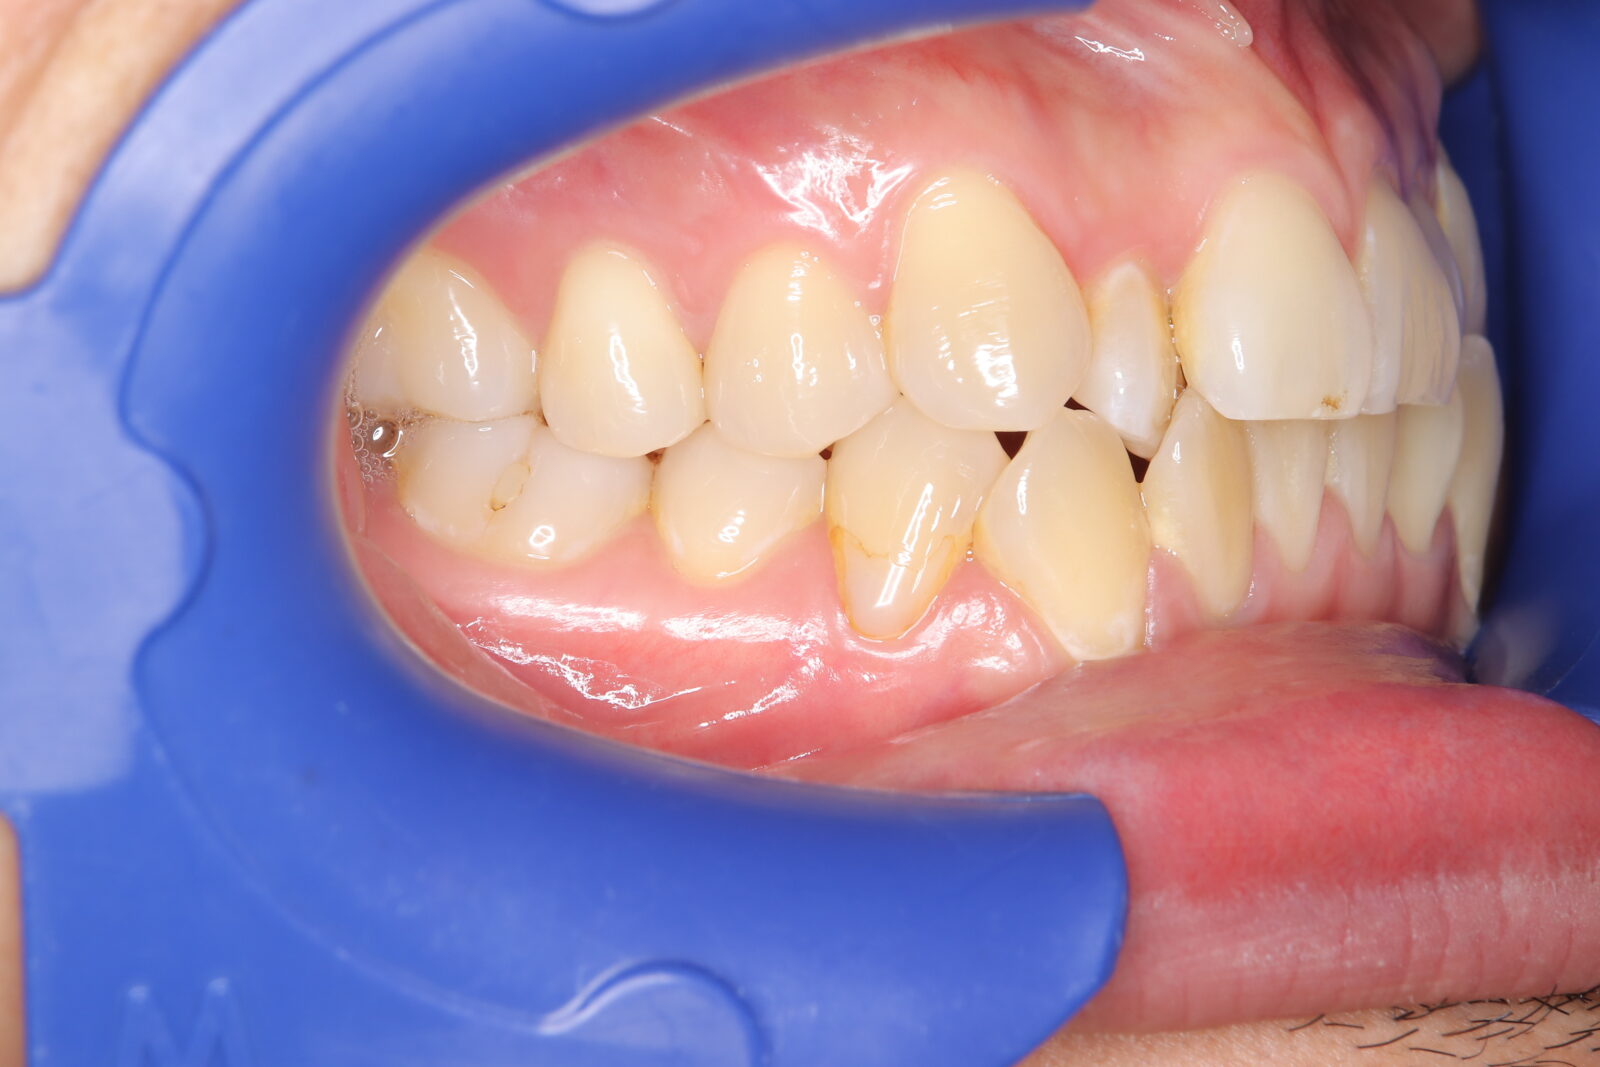

職業柄抜歯をすることができない患者様の症例

職業柄抜歯をすることができないため、小臼歯も親知らずも非抜歯の矯正となりました。 それでは歯を並べるためのスペースを確保できない。歯根の形状を分析し、可能な限り歯冠修復で前歯のサイズを小さくして、歯を動かすためのスペースを作り矯正をスタートした。 下顎前歯歯並びきれないこと、理想的な噛み合わせの獲得は難しいことをご理解いただき治療スタートした。 終了時に初期時の不自由がないことを確認済み。